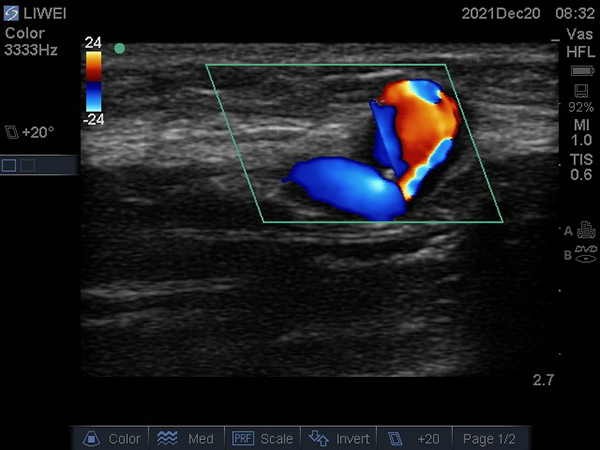

患者李某,男,51歲,規(guī)律血液透析,5年前在徐醫(yī)附院行自體動靜脈內(nèi)瘺(AVF)。近期AVF震顫減弱,流量欠佳,只能達到200ml/min,遂到徐醫(yī)附院就診。術(shù)前超聲檢查示AVF動脈穿刺點上游血管狹窄,長度約4cm,最狹窄處僅有2.5mm,伴吻合口狹窄;颊呓(jīng)過PTA治療,AVF震顫明顯增強,流量達到1793ml/min,完全滿足透析要求,手術(shù)成功。